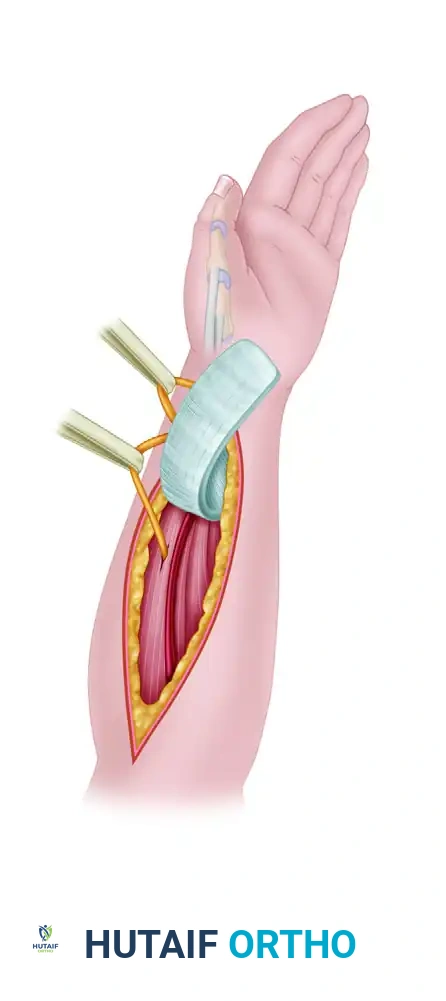

Distally Based Radial Forearm Fascia-Fat Flap

This advanced technique utilizes a local fasciosubcutaneous flap based on the radial artery perforators.

- Flap Harvest: A radial fasciosubcutaneous flap (approximately 4 cm x 12 cm) is harvested from the volar forearm. The superficial branch of the radial nerve and the lateral antebrachial cutaneous nerve are retracted and protected. The flap is turned over 180 degrees distally.

Figure: The distally based radial forearm fascia-fat flap is harvested, protecting the radial artery and local cutaneous nerves.

- Tendon Wrapping: The vascularized fascial flap is wrapped around the scarred APL and EPB tendons to provide a healthy, vascularized gliding bed.

Figure: The fascial flap is wrapped around the APL and EPB tendons.

- Tube Construction: A vascularized fascial tube is created and anchored distally with tacking sutures to reconstruct the extensor retinaculum and prevent subluxation.

Figure: Fascial tube construction is completed, anchoring the flap distally with tacking sutures to restore biomechanical stability.